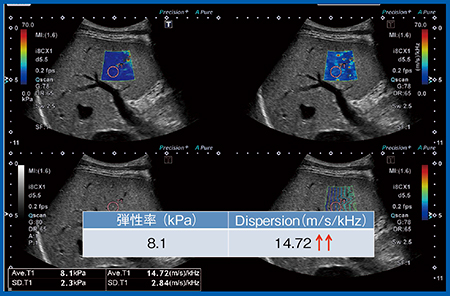

症例3(図10)は急性A型肝炎症例で,血液検査の結果,ASTが6760U/L,ALTが7698 U/Lと高値である。弾性率は8.1kPaとわずかに上昇し,一方,Dispersion slopeは14.72m/s/kHzと著明に上昇していた。

図10 症例3:急性A型肝炎症例の弾性率とDispersion slope

Plt 13.4万,AST 6760,ALT 7698,T-Bil 4.59